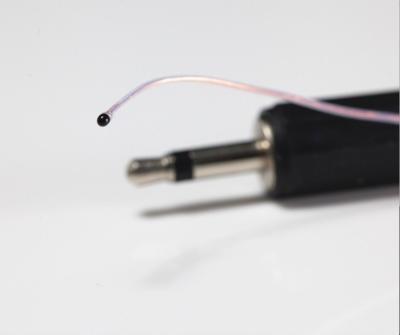

5mW Ntc 5k Thermistor , Low noise iR temperature sensor For intestine

High Light:5k intestine ir temperature sensor, Low Noise ntc 5k thermistor, 5mW ir temperature sensor

5K 10K Medical Temperature Sensor Application Medical Equipment According to application, medical temperature sensor will be grouped into 3 types: body surface temperature sensor, body cavity temperature sensor and disposable body temperature sensor. Body surface temperature sensor is used to measur... View More